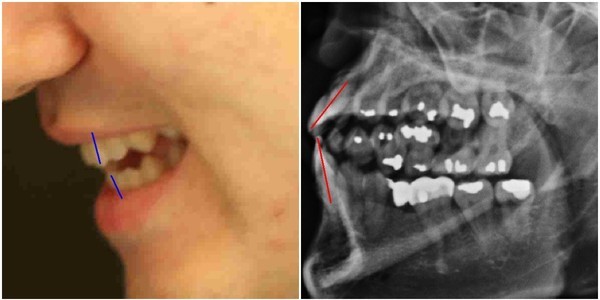

이 사건의 숨겨진 쟁점 중 하나는 ‘박주신씨 구외 엑스레이(이하 치아 엑스레이)에서 나타나는 의혹’이다.박주신씨의 치과진료기록은 풀리지 않는 미스터리로 남아있다.

양승오 박사 등에 대한 검찰의 수사가 진행되던 지난해, 이 사건 피고인들은 박주신씨 치아 X-Ray를 근거로, 박주신씨의 신체를 촬영했다는 X-Ray 속 피사체가 제3의 인물일 가능성을 주장했다.

주신씨의 치아 X-Ray는 허리 MRI 촬영 과정에서 찍힌 X-Ray 사진들 중에서 치아가 보이는 X-Ray 사진이다.

따라서 치아 X-Ray 상에 나타나는 각종 의혹은, 허리 MRI와 더불어 해당 피사체가 주신씨가 아닐 가능성에 무게를 더한다.

피고인들이 치아 X-Ray를 근거로, '피사체 바꿔치기' 의혹을 강하게 제기한 이유는, X-Ray에 나타난 치아의 상태가, 도저히 20대 중반 청년의 것이라고는 보기 힘든 특징을 갖고 있었기 때문이다.

주신씨 치아 X-Ray 사진을 보면, 치아 상태가 매우 불량하다는 사실을 알 수 있다. 치아 2개는 아예 없고, 아말감으로 때운 치아가 무려 14개에 달한다.

- ▲ 박주신씨의 실체 치아 모습과, 주신씨의 치아 상태를 보여주는 엑스레이 사진. ⓒ 뉴데일리DB

- ▲ 박주신씨 치아 엑스레이 분석자료. ⓒ 뉴데일리DB